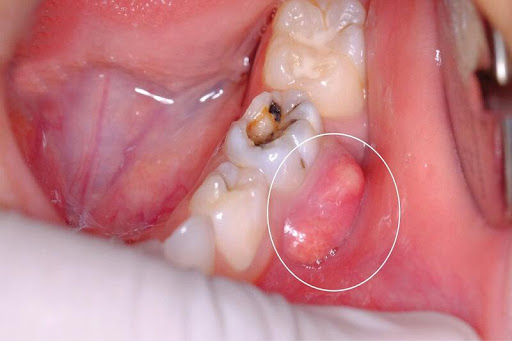

- Có tình trạng sưng nướu, có thể xuất hiện mủ hay sưng cả vùng má. Bạn có thể nhận thấy nướu răng sưng đỏ và đau khi chạm vào. Áp xe răng thì có thể bị khối phồng mềm chứa mủ viêm.

Viêm quanh cuống

- Phẫu thuật cắt chóp răng: Trong những trường hợp điều trị tủy bị thất bại hoặc tổn thương lớn vùng chóp răng thì sẽ phải thực hiện phẫu thuật cắt chóp răng.